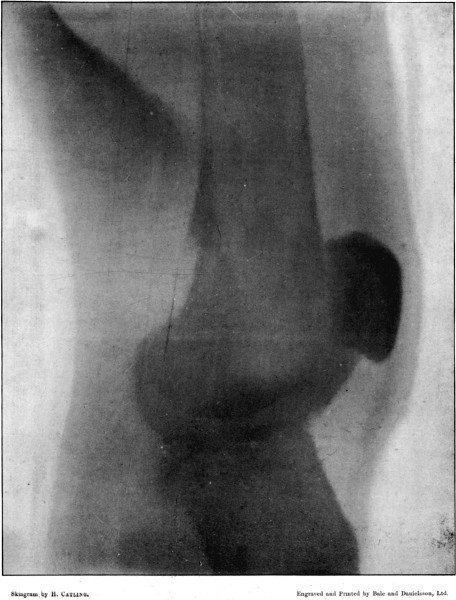

3. Punctured Fracture of Clavicle162

4. Comminuted Fracture of Shaft of Humerus180

5. Comminuted Fracture of Humerus accompanied by an Explosive Exit182

6. Comminuted Fracture of Humerus due to Oblique Impact184

7. Same Fracture healed186

8. Low Velocity Fracture of Humerus With Retained Bullet188

9. Localised Fracture of Humerus Showing Fragmentation of the Bullet190

10. Wedge-shaped Fracture of the Radius192

11. Fracture of the Metacarpus, showing Fragmentation of the Bullet194